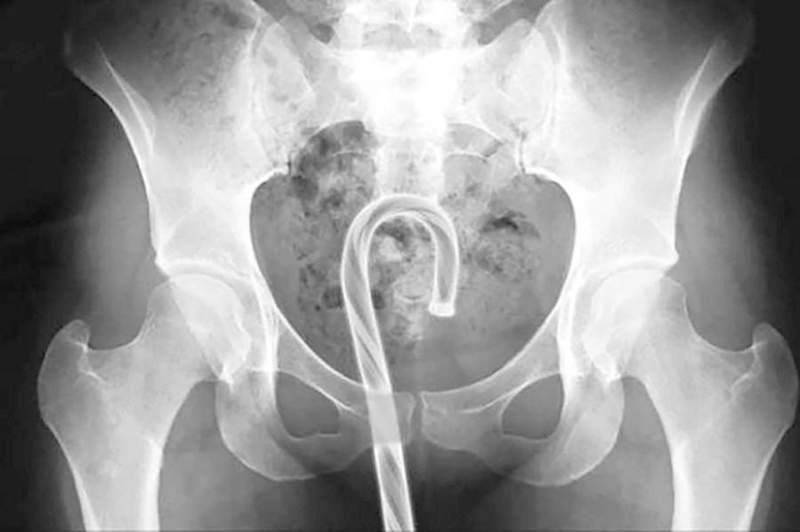

X光机下拍到的各种异物

老二・蜡笔・原子笔、笔盖・筷子・玩具尖锐的一端・棒棒糖的棒子・磁铁・螺丝起子・第四台的铜轴电线・髮夹・结婚戒指